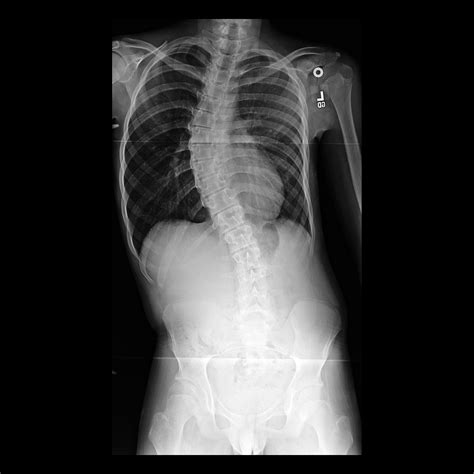

Free Scoliosis Screening - Scoliosis Physiotherapy